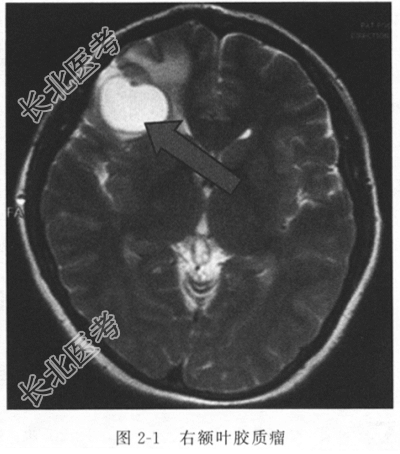

辅助检查 E4A检验示血钾2.7mmol/L、血钠134.5mmol/L。CT及MRI检查结果提示右侧额叶胶质瘤术后复发可能(图2-1)。

入院诊断 右额叶胶质瘤术后复发。